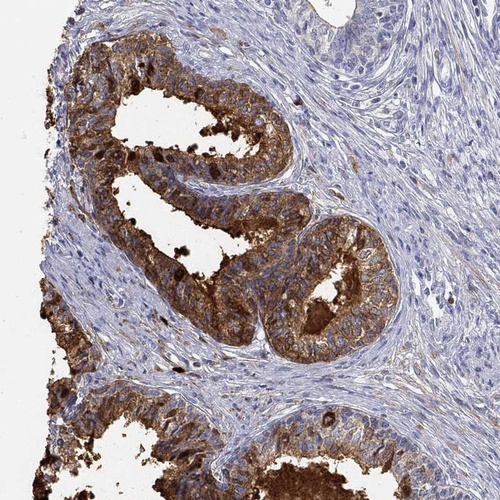

Immunohistochemistry analysis in human prostate and liver tissues using HPA078464 antibody. Corresponding ANO7 RNA-seq data are presented for the same tissues.